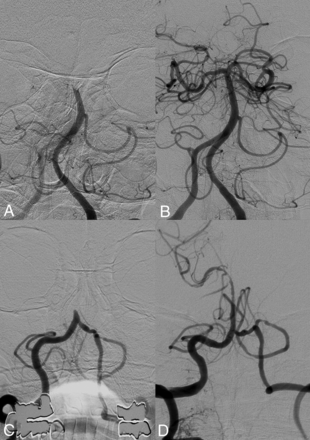

The treatment and clinical outcomes according to the presence of the clot meniscus sign are summarized in the Online Supplemental Data. The clot meniscus sign was seen in 59.6% (96/161) of patients. In the patients positive for the meniscus sign, the CA group showed a shorter procedural time (44 versus 26 minutes; P = .018), a lower total number of passes (median, 2 versus 1; P = .041), a higher rate of complete recanalization (58.8% versus 85.7%; P = .021), and a higher rate of first-pass effect (27.9% versus 53.6%; P = .031) compared with the SR group (Fig 2). After PSM, the CA group was associated with a higher complete recanalization rate (59.3% versus 85.7%, P = .033) and a tendency toward a higher first-pass effect (29.6% versus 53.6%, P = .084). No significant differences in the outcomes were noted between the SR and CA groups in the patients negative for the meniscus sign except for the shorter procedural time in patients with PSM and CA (90 versus 56 minutes, P = .02).

Pre- (A) and post- (B) thrombectomy images of a basilar artery occlusion in a patient with the positive clot meniscus sign. Complete recanalization was achieved using a single attempt of contact aspiration. Pre- (C) and post- (D) thrombectomy images of a patient with a basilar artery occlusion with the negative clot meniscus sign. Following an unsuccessful first-line approach with contact aspiration, multiple attempts of rescue thrombectomy were performed with the stent retriever, revealing an underlying atherosclerotic stenosis (not shown). Recanalization was achieved by permanent stent placement.